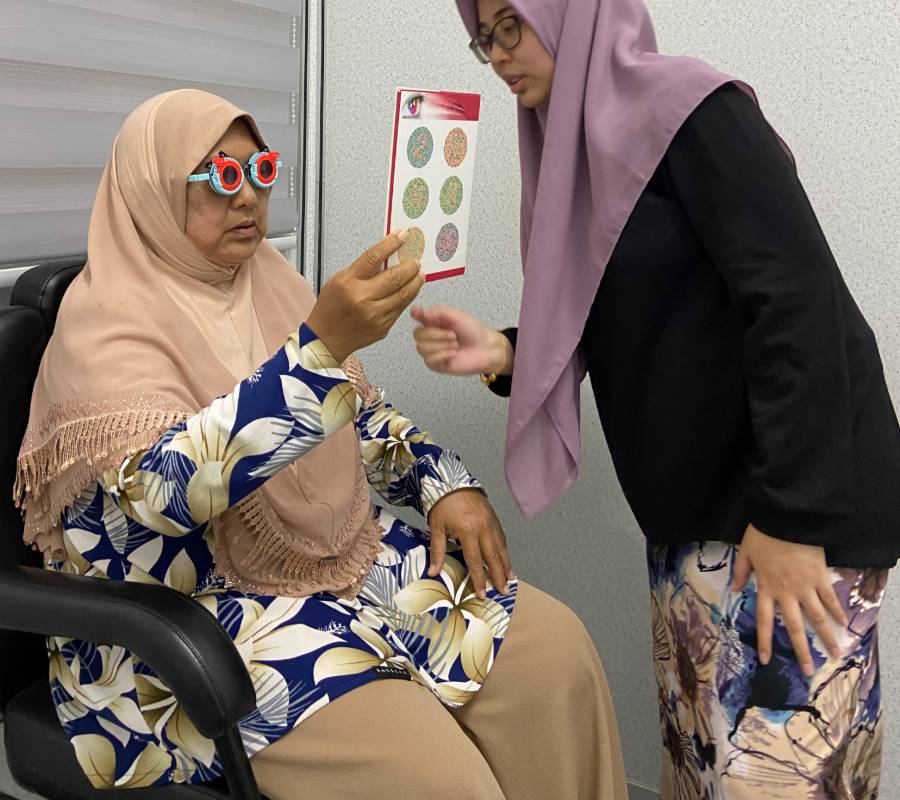

Pakar Optometri Berpengalaman

Servis Holistik Mesra Keluarga

Pemeriksaan menyeluruh ke atas bahagian hadapan (anterior) dan belakang (posterior) mata—termasuk kornea, kanta, iris, retina serta saraf optik.